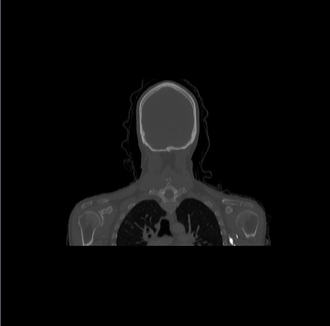

| − | [[ | + | [[File:Axial_orig_image.png|||330px|||]] [[File:Coronal_orig_image.png|||330px|||]] [[File:Sagittal_orig_image.png|||330px|||]] |

- Datasets